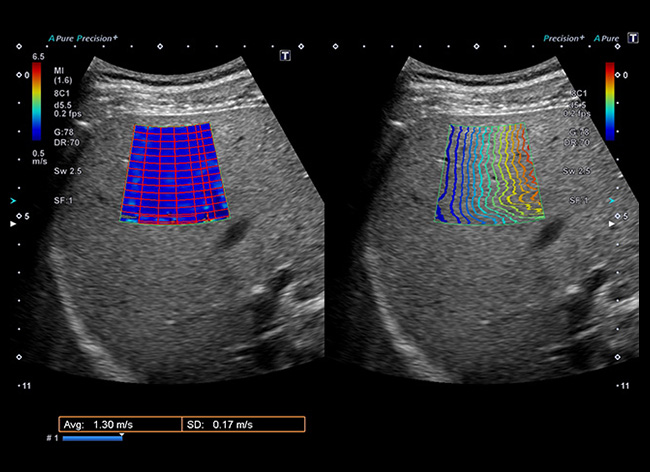

Саме застосування УЗД-апаратів від CANON MEDICAL повністю змінило стандарти діагностики фіброзу печінки — еластографія використовує ультразвук в реальному часі для оцінки еластичності тканин і є швидким, простим, відтворюваним і надійним методом неінвазивної оцінки фіброзу печінки.

Тобто еластографія – сучасний неінвазивний метод ультразвукової діагностики, який дозволяє оцінити ступінь фіброзу печінки при хронічних її захворюваннях.

Для правильного трактування отриманих результатів нагадуємо вам, шановні колеги, шкалу фіброзу, адаптовану та рекомендовану для використання на приладах CANON MEDICAL.

Ultrasound Shearwave for Staging Liver Fibrosis: Preliminary Results of a Prospective Multicenter European Study

Stage Fibrosis Stage Speed (m/s) Elasticity (kPa)

F0-F1 Non significant < 1,54 < 7.1

≥ F2 Significant 1,54 - 1,78 7,1 – 9,5

≥ F3 Advanced 1,78 – 1,87 9,5 – 10.5

F4 Cirrhosis > 1,87 > 10.5